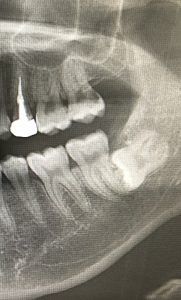

一般的なものでは埋もれている親知らずの抜歯や、虫歯などの理由で根っこだけになってしまった歯の抜歯があります。

※この程度の親知らずであれば特に問題はありません